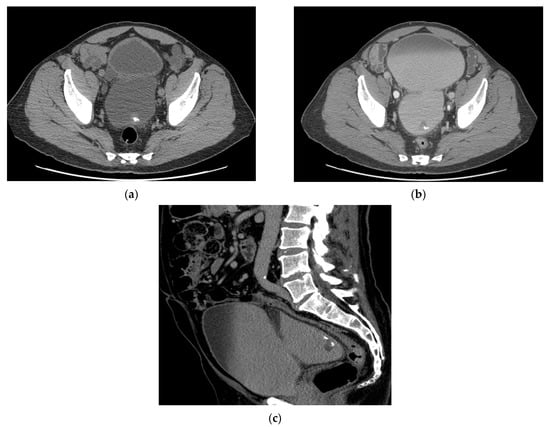

5.1. Computed Tomography (CT)